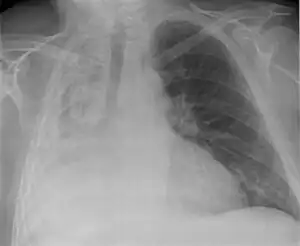

| Atelectasis of a person's right lung | |

Clinically significant atelectasis is generally visible on chest X-ray; findings can include lung opacification and/or loss of lung volume. Post-surgical atelectasis will be bibasal in pattern. Chest CT or bronchoscopy may be necessary if the cause of atelectasis is not clinically apparent. Direct signs of atelectasis include displacement of interlobar fissures and mobile structures within the thorax, overinflation of the unaffected ipsilateral lobe or contralateral lung, and opacification of the collapsed lobe. In addition to clinically significant findings on chest X-rays, patients may present with indirect signs and symptoms such as elevation of the diaphragm, shifting of the trachea, heart and mediastinum; displacement of the hilus and shifting granulomas.[10]

Atelectasis of the right lower lobe seen on chest X-ray.